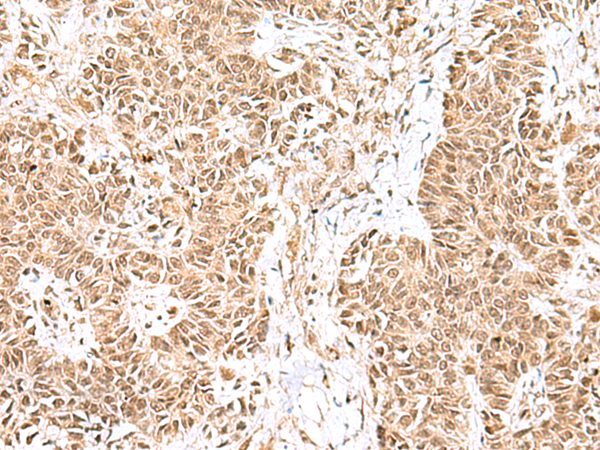

IHC positive control: |

Human esophagus cancer and Human ovarian cancer |

IHC Recommend dilution: |

25-100 |